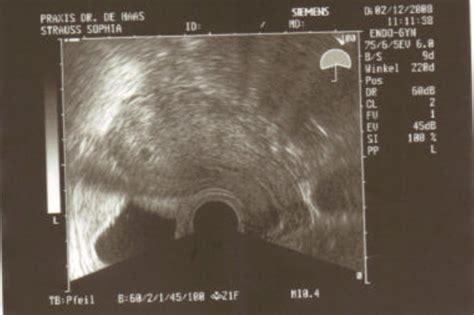

Das Ersttrimester-Screening (ETS) wird zwischen der 11+0 und 13+6 Schwangerschaftswoche durchgeführt und kombiniert eine Ultraschalluntersuchung mit einer Blutuntersuchung der werdenden Mutter.

Ultraschalluntersuchung im ersten Trimester

Bereits in dieser frühen Phase der Schwangerschaft können mittels Ultraschall schwere Fehlbildungen der Organe oder des Skeletts durch eine frühe Feindiagnostik zum Teil erkannt werden. Ein wichtiger Bestandteil ist die gezielte Ultraschallmessung der Nackentransparenz (NT). Ein erhöhter NT-Wert ist keine eigene Erkrankung, kann aber hinweisend auf eine Chromosomenstörung oder genetische Erkrankung sein.

Für die Untersuchung eines Kindes wird ein Zeitfenster von 30-45 Minuten veranschlagt. Darin sind die ausführliche Aufklärung, der Ultraschall selbst und die Besprechung der Ergebnisse sowie die Erstellung eines Berichts enthalten. Die Untersuchung wird in der Regel über die Bauchdecke durchgeführt. In seltenen Fällen kann auch ein vaginaler Ultraschall erforderlich sein. Es ist mitunter mit Wartezeiten zu rechnen, da der Zeitumfang einzelner Untersuchungen nicht immer exakt vorhersehbar ist.